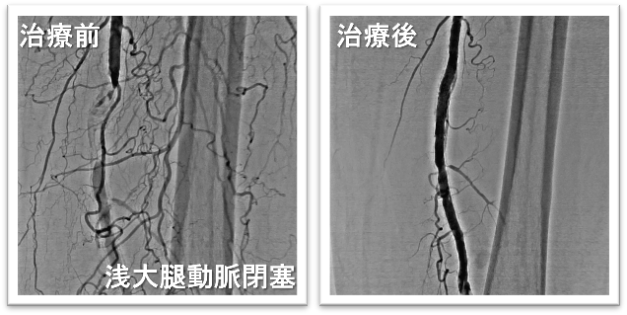

末梢動脈治療において、EVTは下肢血流の回復に必要不可欠な治療です。当院では石灰化・閉塞病変など複雑病変にも対応し、年間100件のEVTを実施しています。